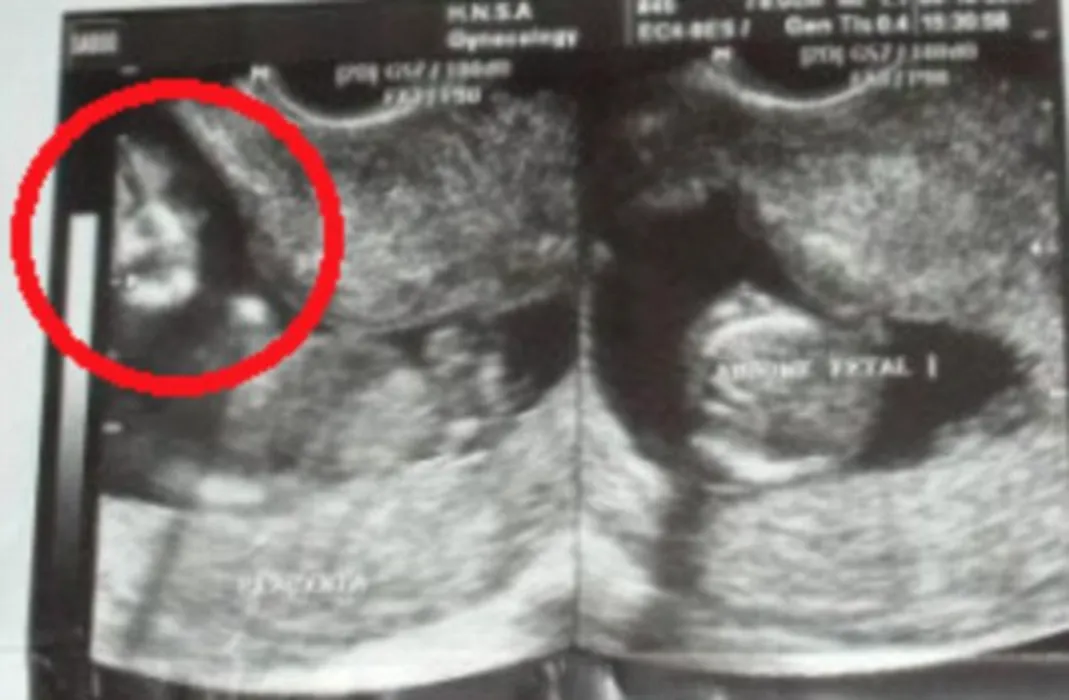

Ce surpriză a avut o gravidă când a făcut ecografie. „Semăna prea mult cu ea pentru a fi o coincidență”